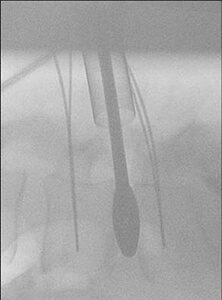

Διεγχειριτικές ακτινογραφίες του ασθενούς μετά την επέμβαση.